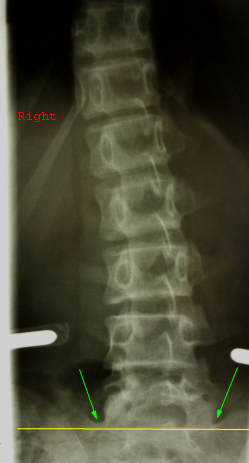

Пример

разметки края крыла подвздошной кости у ребенка 7 лет (ядра окостенения не

определяются, следовательно признак Риссера равен 0). На левой стороне снимка для примера проведена полстая белая линия,

имитирующая ядро окостенения гребня крыла подвздошной кости для признака

Риссера III. Маленький белый овал имитирует ядро окостененения

передней подвздошной ости.